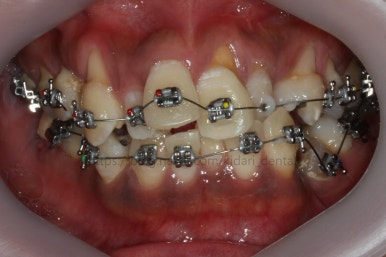

부산치아교정 키다리아저씨치과에 처음 내원 당시의 입안 모습입니다.

여러 가지 문제점이 있는데 하나씩 살펴볼게요.

치열이 많이 삐뚤하네요.

많이 삐뚠 상태에서 장기간 사용하다 보면 안좋은 방향으로 치아가 힘을 받게 되고 마모나 치아 목부분 패임이 심해집니다.

양치가 힘들어요. 양치가 힘들다 보니 세게 닦게 되고 치아 손상은 더 심해져요. 25세의 나이였는데 나이에 비해서 치아나이가 굉장히 많은거죠.

화살표 부분에 원래 송곳니가 있어야 되는데 보이질 않네요. 결손치아일 수도 있고 매복치아일 수도 있겠어요.

왼쪽 위 어금니도 한 개가 없어서 빈공간이 약간 남아있어요.

왼쪽 아래 작은 어금니는 아래쪽으로 많이 꺼져있네요.

이런 경우 X-ray 도 면밀히 관찰해 줘야 합니다.